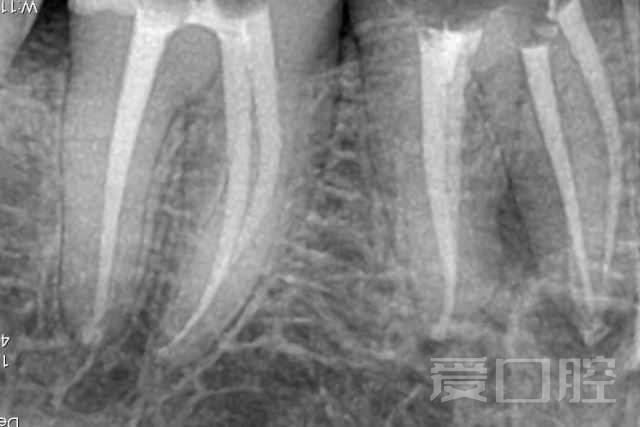

看个根管治疗+冠修复 —— 下颌5、6、7